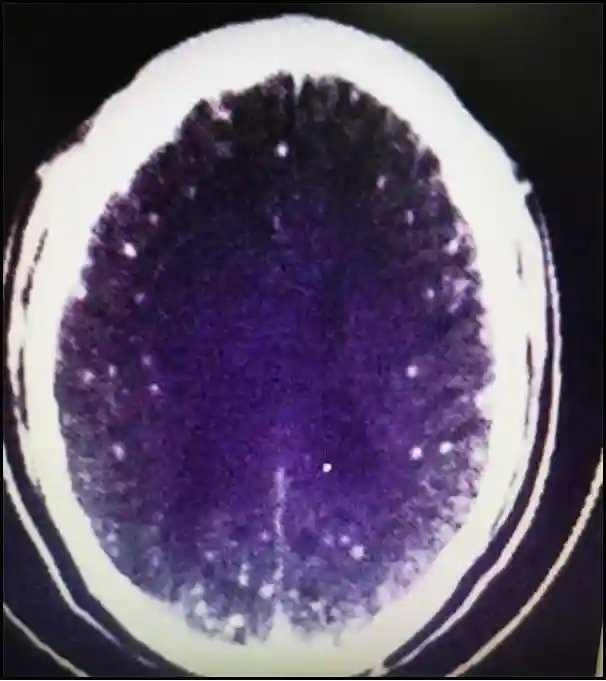

结果发现,两侧大脑半球多发病变,结合血和脑脊液中囊虫抗体阳性,诊断为脑囊虫病。

颅内CT显示有多个白点病变